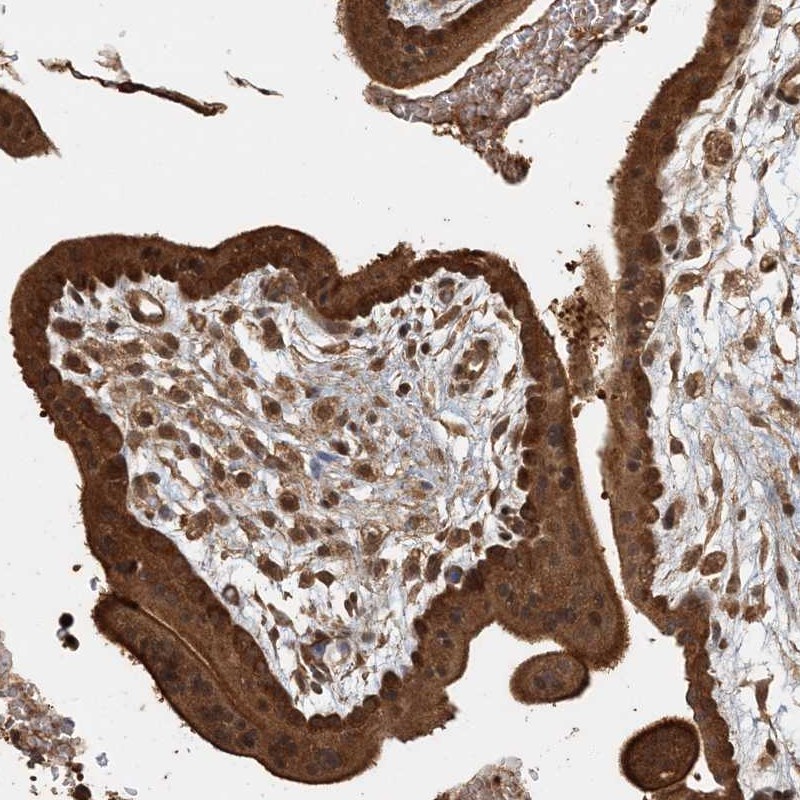

Immunohistochemical staining of human placenta shows strong cytoplasmic and membranous positivity in trophoblastic cells.